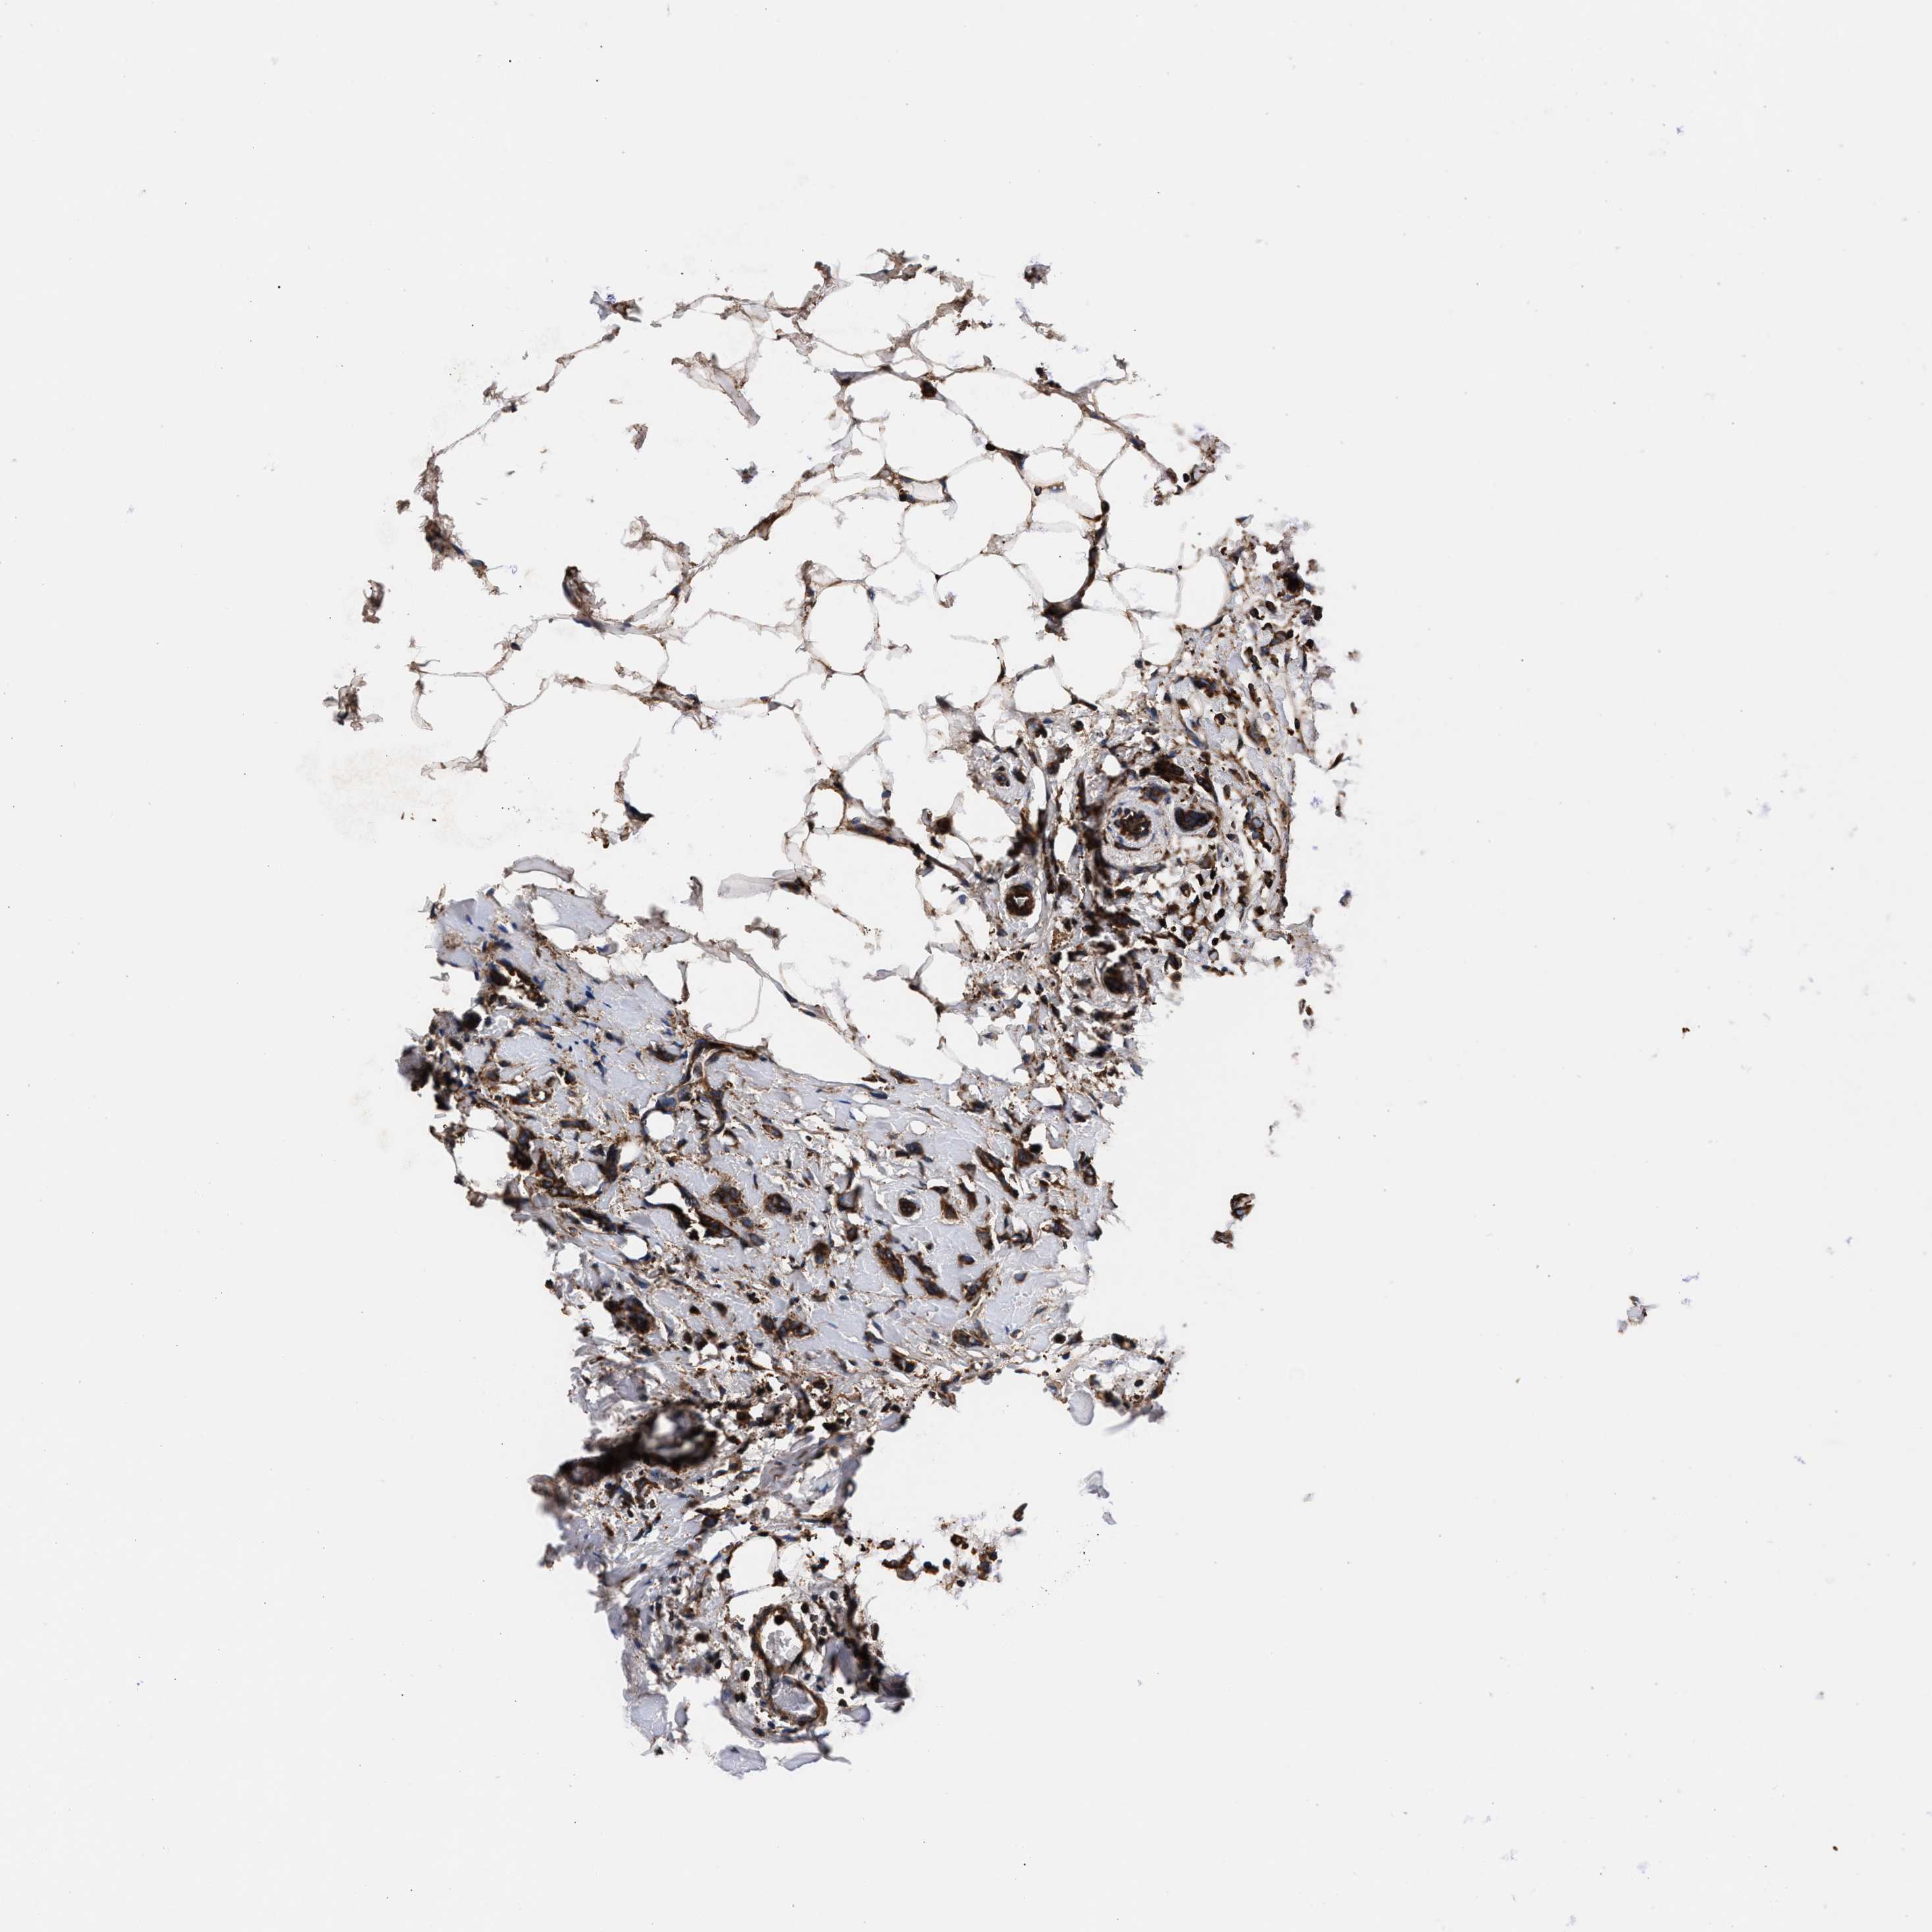

BRCA TCGA BRCA VALIDATION PROTEIN EXPRESSION

ANTIBODIES

AND

VALIDATION